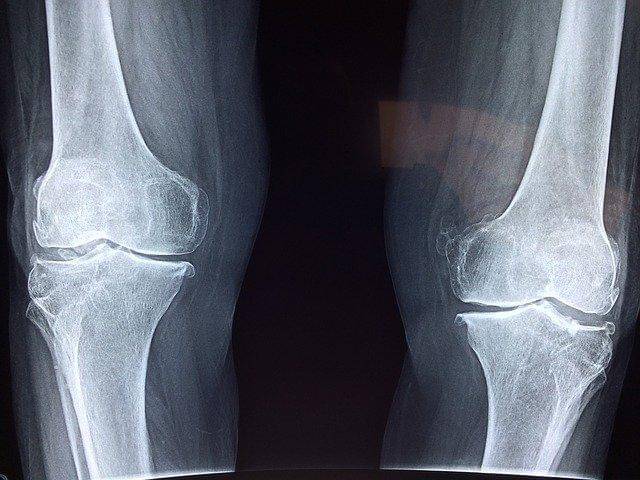

1. Kalsium banyak ditemukan di tulang dan gigi

Sekitar 99% kalsium di dalam tubuh ditemukan di tulang dan gigi. Nutrisi yang satu ini sangat berperan penting dalam pertumbuhan tulang. Kebutuhan kalsium sangat tinggi di masa pertumbuhan hingga mencapai usia 25 tahun. Lalu, kebutuhan kalsium akan menurun seiring bertambahnya usia.

Seseorang yang kekurangan asupan kalsium sebelum usia 25 tahun akan lebih mudah terkena risiko osteoporosis.